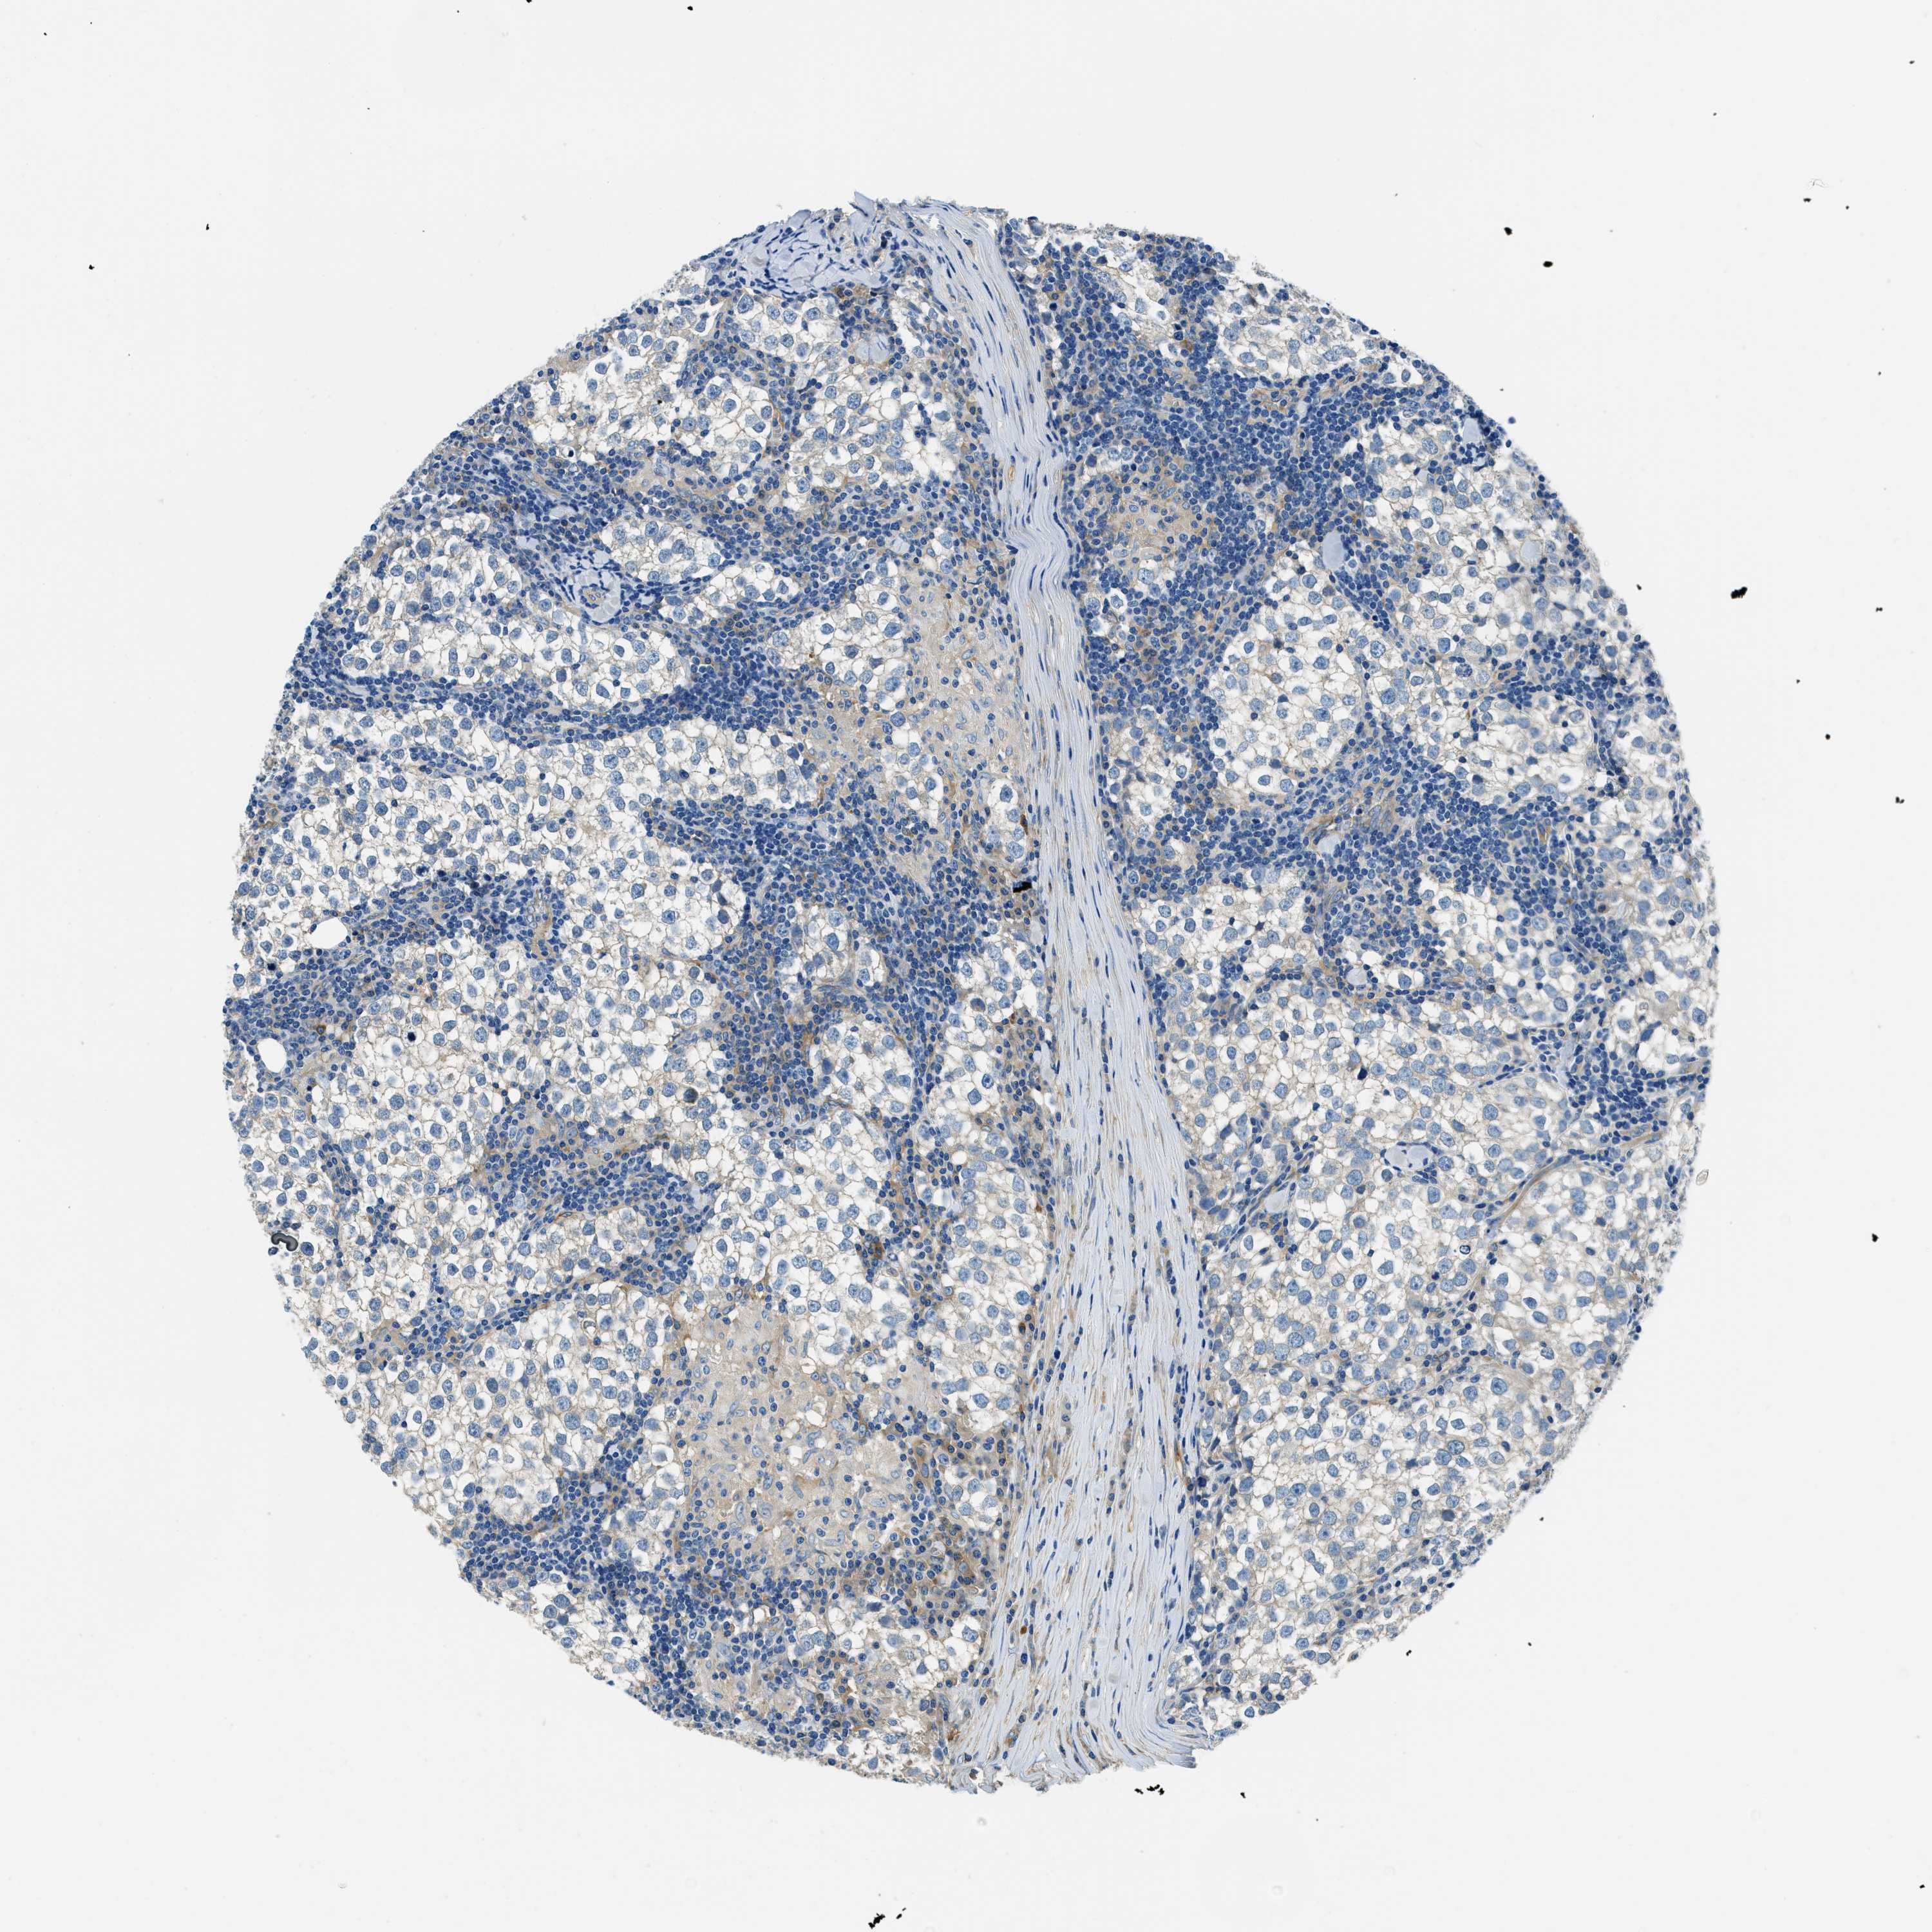

TESTIS CANCER - Protein expressioni

A mouse-over function shows sample information and annotation data. Click on an image to view it in a full screen mode. Samples can be filtered based on level of antibody staining by selecting one or several of the following categories: high, medium, low and not detected. The assay and annotation is described here.

Note that samples used for immunohistochemistry by the Human Protein Atlas do not correspond to samples in the TCGA dataset.

Antibody stainingi

Antibody staining in the annotated cell types in the current human tissue is reported as not detected, low, medium, or high, based on conventional immunohistochemistry profiling in selected tissues. This score is based on the combination of the staining intensity and fraction of stained cells.

Each image is clickable and will lead to virtual microscopy that enables deeper exploration of all samples and also displays staining intensity scores, fraction scores and subcellular localization as well as patient and tissue information for each sample.

Antibody HPA018116

Staining

High

Medium

Low

Not detected

Intensity

Strong

Moderate

Weak

Negative

Quantity

>75%

75%-25%

<25%

None

Location

Nuclear

Cytoplasmic/membranous

Cytoplasmic/membranous,nuclear

Carcinoma, Embryonal, NOS

Seminoma, NOS